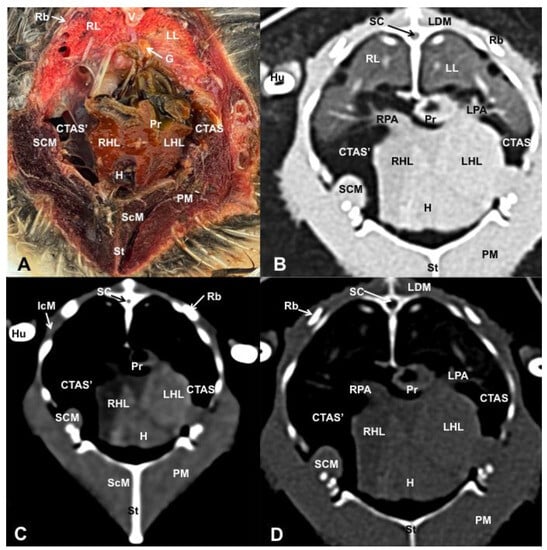

3.1. Anatomical Dissections and Cross-Sections

3.2. Computed Tomography Images